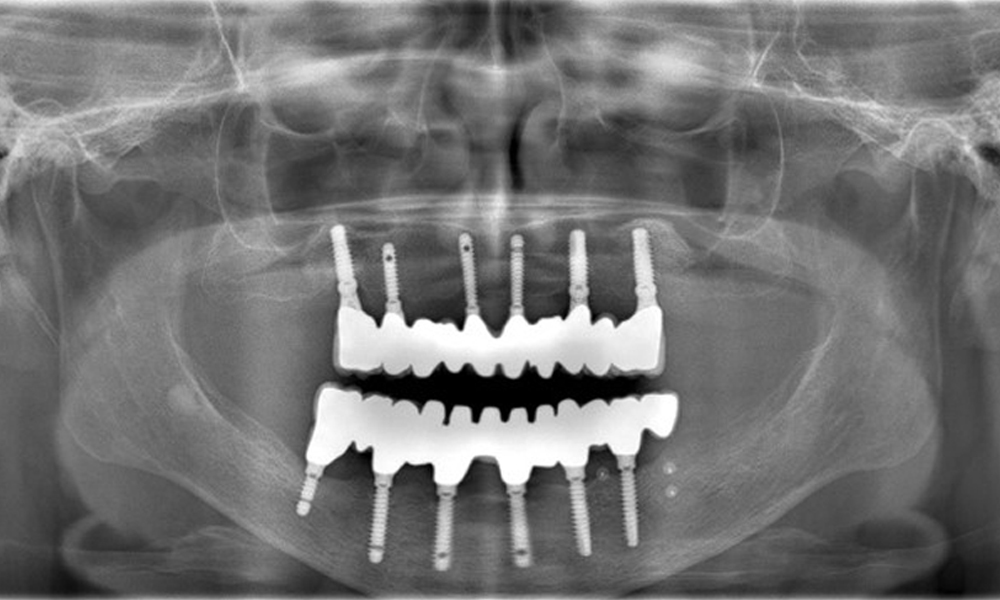

Versorgungen: Implantate regio 011, 013, 015, 021, 023, 025, 031, 033, 035, 042, 044, 046

Die Röntgenaufnahmen zeigen den Knochenabbau.

Abb. 2: Die Röntgenaufnahmen zeigen den Knochenabbau.